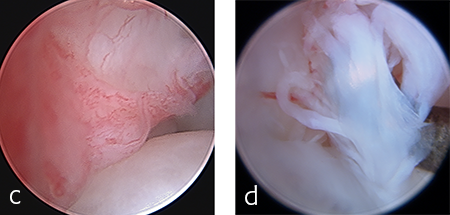

The patient was anesthetized and placed in ventral recumbency. Arthroscopic evaluation of the right antebrachiocarpal joint revealed synovitis and partial tearing of the palmar radiocarpal and ulnocarpal ligaments (Fig 4). A decision was made to perform a pancarpal arthrodesis due to arthroscopic evidence of damage at this level of the joint. A dorsal approach was made to the right carpus. The articular cartilage was debrided at all levels of the carpus. An autogenous cancellous bone graft was harvested form the right proximal humerus and was applied at the arthrodesis site.